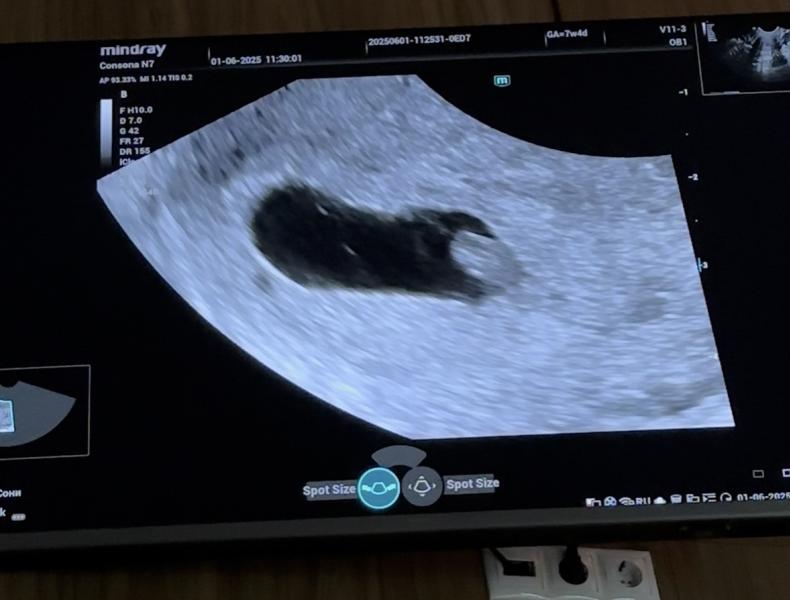

Сходила я на узи, тревожная мать🙈 Все хорошо, сердечко стучит на узи она разглядывала, говорит что как будто есть перегородка, но второго эмбриона нет, сказала что либо в начале должен был быть, или появится ещё🙈 Какова вероятность что сейчас нету, а потом появится второй? Уже 7,4 недели

(На втором фото видно перегородку)

Я ходила в 6-7 недель на УЗИ, у меня было одно плодное яйцо

В 10 недель пошла на уточнение срока, стало 2👀